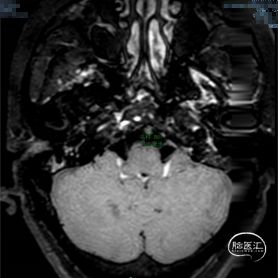

➢ 入院脑MRI

➢ 脑血管造影检查

➢ 高分辨磁共振